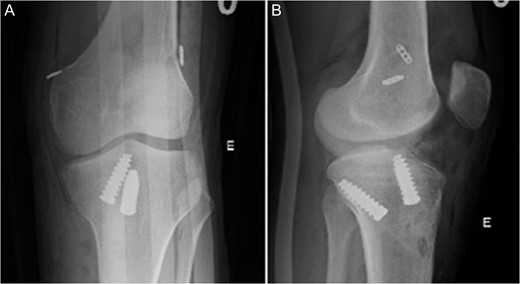

Radiographic image in AP (A) and lateral view (B) of left knee after surgery.